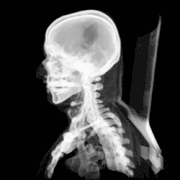

Injuries and treatment

Injuries to the brain can be life-threatening. Normally the skull protects the brain from damage through its high resistance to deformation; the skull is one of the least deformable structures found in nature, needing the force of about 1 ton to reduce its diameter by 1 cm.[19] In some cases of head injury, however, there can be raised intracranial pressure through mechanisms such as a subdural haematoma. In these cases, the raised intracranial pressure can cause herniation of the brain out of the foramen magnum ("coning") because there is no space for the brain to expand; this can result in significant brain damage or death unless an urgent operation is performed to relieve the pressure. This is why patients with concussion must be watched extremely carefully. Repeated concussions can activate the structure of skull bones as the brain's protective covering.[20]

Dating back to Neolithic times, a skull operation called trepanning was sometimes performed. This involved drilling a burr hole in the cranium. Examination of skulls from this period reveals that the patients sometimes survived for many years afterward. It seems likely that trepanning was also performed purely for ritualistic or religious reasons. Nowadays this procedure is still used but is normally called a craniectomy.

In March 2013, for the first time in the U.S., researchers replaced a large percentage of a patient's skull with a precision, 3D-printed polymer implant.[21] About 9 months later, the first complete cranium replacement with a 3D-printed plastic insert was performed on a Dutch woman. She had been suffering from hyperostosis, which increased the thickness of her skull and compressed her brain.[22]